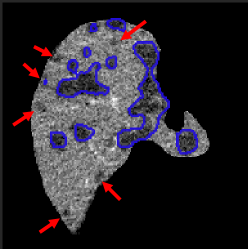

After having the liver segmented, we might directly apply a 3D segmentation network to extract the liver lesions. However, a 3D Network operating only in the liver region is still computationally expensive and may suffer from the problem of lacking 3D training scans. In order to mitigate these issues, we propose to use a mixed network to handle the segmentation of large and small lesions separately. In particular, we use a 2D network to scan slice-by-slice and predict larger tumors if present. However, this method is not sufficient for predicting small lesions, as the false positive examples shown in Fig. 3. This happens due to the appearance of the small lesion matching that of other tissues or vessels on 2D liver slices. A 3D network learning from cropped volumes with small lesions can reduce such false positives, because it leverages the observation that the location of the tissue or vessel appears to travel considerably in-between slices whereas the liver lesion constantly appears to be roughly stationary across slices. Regarding the threshold of the lesion size used to separate the large and small lesions, it may vary for different applications and datasets. Here, we set the threshold as a resolution of by experimentally testing on the LiTS dataset, which greatly balances the prediction accuracy and the computational efficiency.

Large Lesion Segmentation. We use another 2D CompNet like the one used for the liver segmentation (Fig. 2) to extract lesions larger than from the input slices with the liver only. Since this network takes care of the prediction of large lesions, we clean the training masks by using the component labeling [2] to remove all small lesion masks, whose horizontal and vertical dimensions are both less than or equal to 32 on a 2D slice, for every slice. In the test phase we also remove the detected lesions less than using the component labeling.